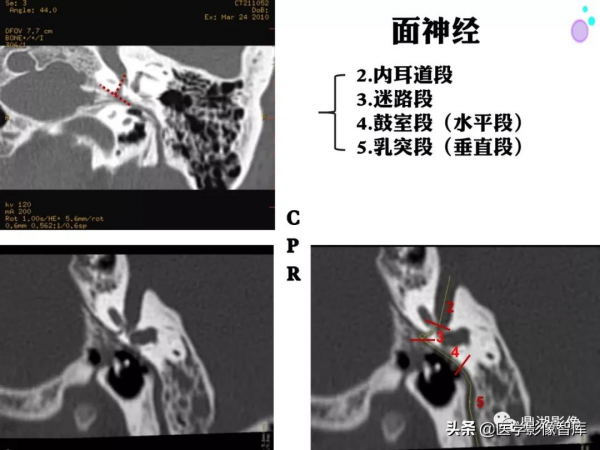

顳骨